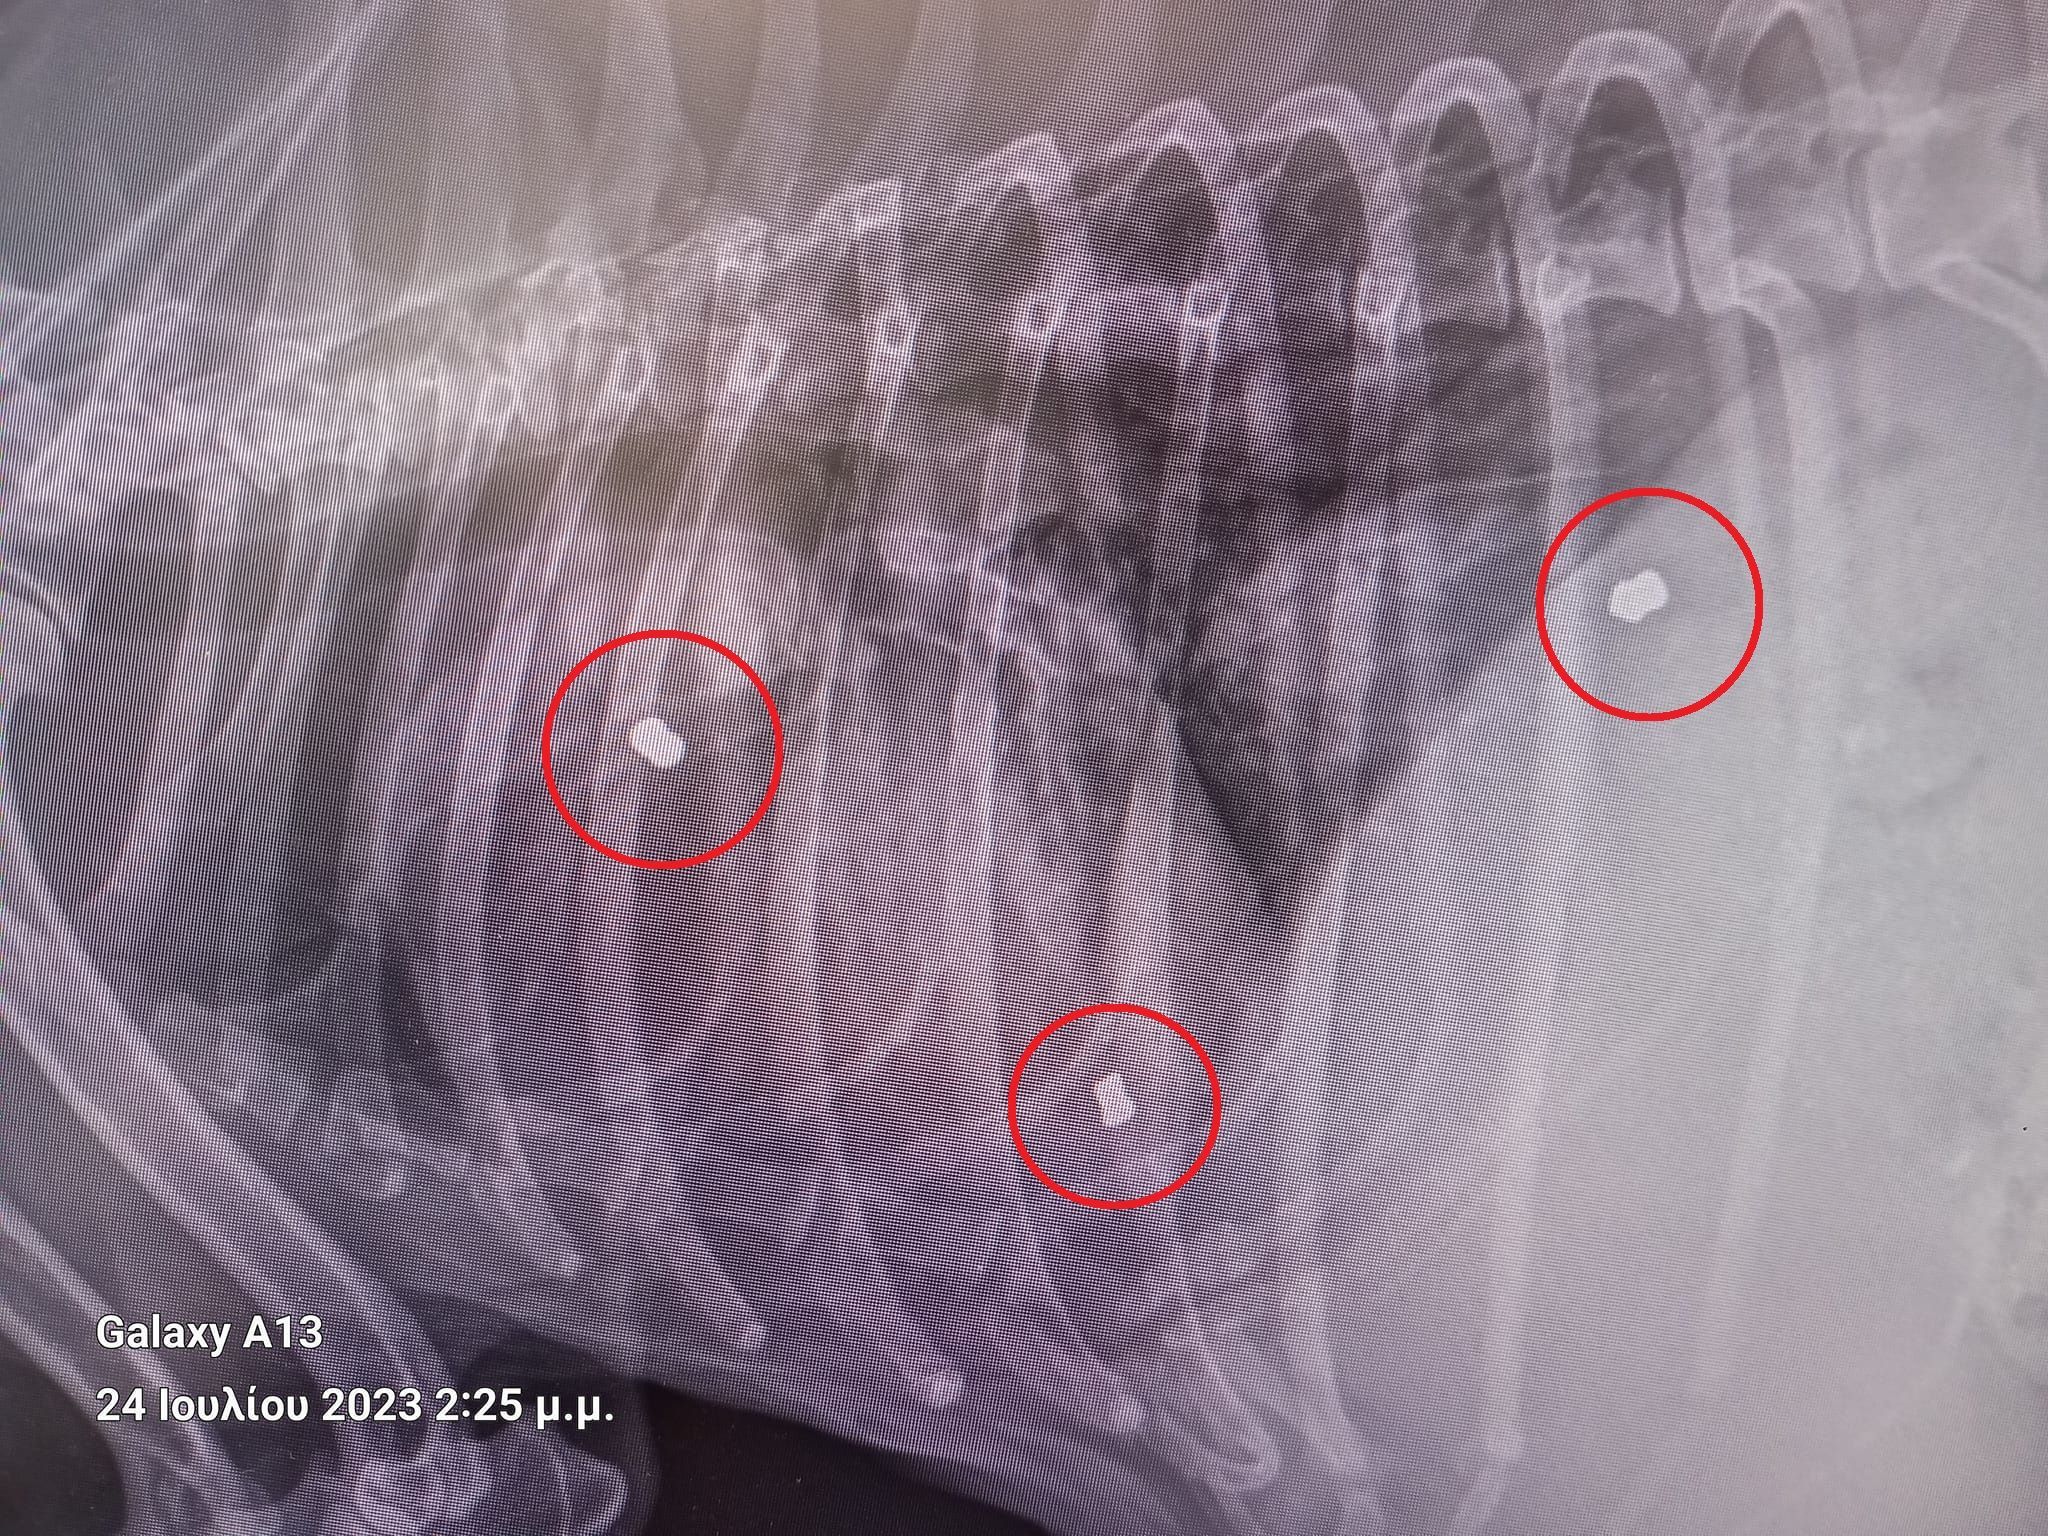

Έκκληση για να καλυφθούν τα έξοδα περίθαλψης του σκύλου που βρέθηκε σοβαρά άρρωστος (καρδιακή ανεπάρκεια) στο χωριό Άργιλος Κοζάνης και – όπως αποδείχτηκε – έχει πυροβοληθεί τρεις φορές με αεροβόλο απευθύνει η Βούλα Τζάνου, ιδρύτρια της Α.Μ.Κ.Ε. «ΑΔΕΣΠΟΤΑ ΣΕΪΧ ΣΟΥ».

Το ζώο είναι πυροβολημένο, έχει ασκίτη δηλαδή μεγάλη ποσότητα υγρού στην κοιλιακή κοιλότητα και καρδιακή ανεπάρκεια...

ΜΕ ΠΗΡΑΝ ΤΗΛ ΚΑΙ ΤΟ ΖΩΟ ΚΑΤΕΒΗΚΕ ΚΤΗΝΙΑΤΡΙΚΗ ΚΛΙΝΙΚΗ ΑΓΑΘΑΓΓΕΛΙΔΗ !!! ΤΗΝ ΠΑΡΑΚΟΛΟΥΘΩ ΜΕΡΕΣ..... ΤΟ ΚΟΡΙΤΣΑΚΙ ΕΧΕΙ ΧΤΥΠΗΘΕΙ ΤΡΕΙΣ ΦΟΡΕΣ ΔΕΝ ΞΕΡΩ ΑΠΟ ΤΙ.... 3 ΣΚΆΓΙΑ ΜΕΣΑ ΤΗΣ!!!! ΣΗΜΑΊΝΕΙ ΟΤΙ ΤΟ ΑΠΟΒΡΑΣΜΑ ΉΘΕΛΕ ΝΑ ΤΟ ΤΕΛΕΙΩΣΕΙ !!!

Το ζώο έχει πυροβοληθεί τρεις φορές με αεροβόλο...

Το ζώο έχει πυροβοληθεί τρεις φορές με αεροβόλο...